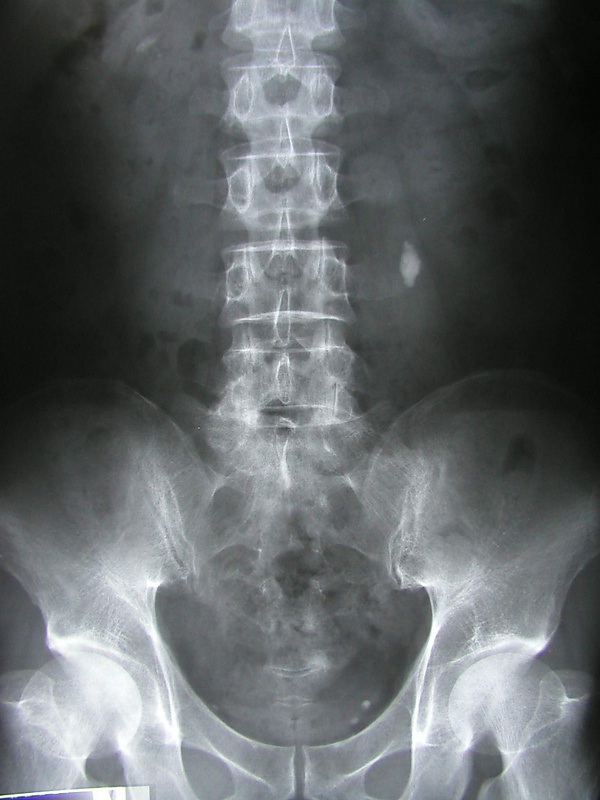

Самые популярные и информативными способы диагностики МКБ — лучевые методы исследования, среди которых:

- Урография обзорная и экскреторная (с контрастом)[10],

- Рентген (ретроградная уретеропиелография),

Урография — рентгеновский метод исследования. Обзорная урография позволяет определить общую картину, установить наличие конкрементов. Экскреторный рентген почек проводится с введенное в организм контрастного вещества, этот метод даёт больше информации о функции почек и мочеточников, также позволяет выявить камни.